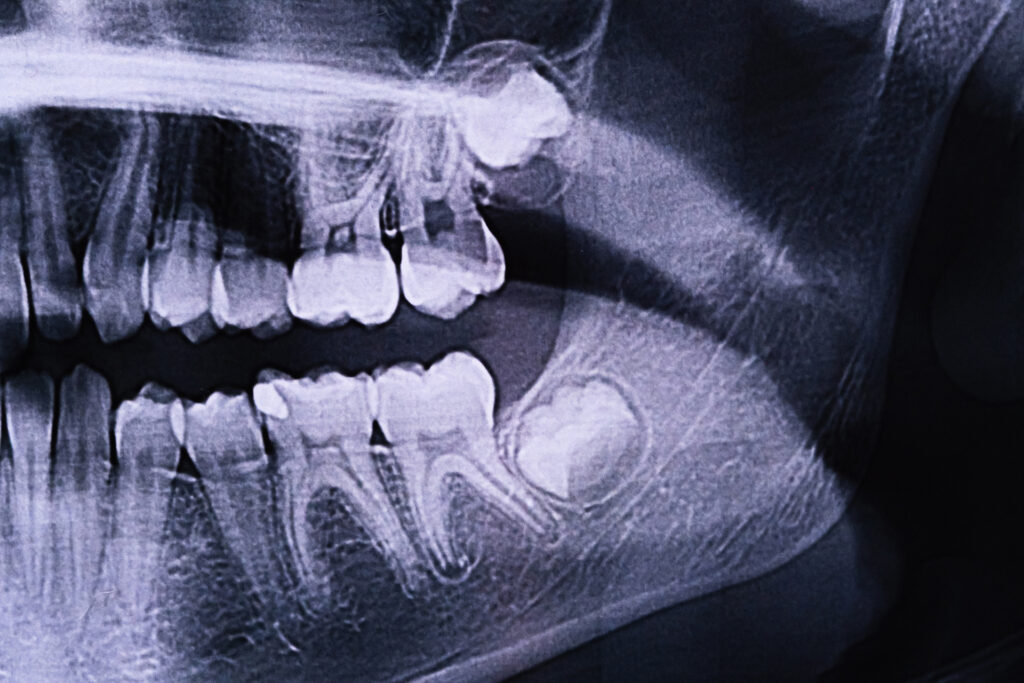

Impacted wisdom teeth are a strong predictor of infection problems. Impaction occurs when there is not enough jaw space for the tooth to emerge fully, causing partial or full entrapment under the gum line.

Different impaction types have their own infection risks. Partial impaction creates bacteria-trapping pockets, making a partially impacted wisdom tooth more prone to infection. Complete impaction can lead to the formation of a cyst. Angular impaction damages adjacent teeth and creates hard-to-clean spaces. Horizontal impaction, where teeth lie sideways and press against the second molars, is the most problematic.

Dental X-rays and panoramic imaging can identify impaction patterns early, allowing for preventive treatment before symptoms develop.

Dentists use multiple approaches to diagnose wisdom tooth infections. Clinical examination includes visual inspection, assessment of swelling and gentle palpation to identify tender areas and abscesses.

Advanced imaging provides crucial information about the extent of the infection and the tooth’s positioning. Digital X-rays show bone loss and decay patterns. Panoramic radiographs provide a comprehensive view of all wisdom teeth, helping to identify current problems and predict future complications. Imaging also helps assess the condition of nearby teeth that may be affected by wisdom tooth infection.